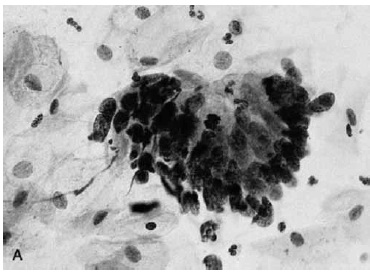

Nas questões de números 46 a 60, assinale a alternativa que melhor corresponde ao diagnóstico do quadro microscópico apresentado.